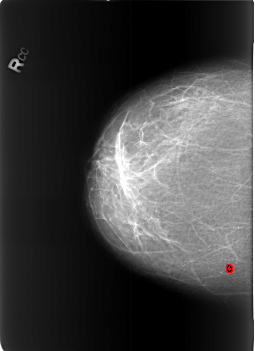

FILE: B_3453_1.RIGHT_CC.OVERLAY

TOTAL_ABNORMALITIES 1

ABNORMALITY 1

LESION_TYPE CALCIFICATION TYPE SKIN DISTRIBUTION REGIONAL

ASSESSMENT 2

SUBTLETY 3

PATHOLOGY BENIGN_WITHOUT_CALLBACK

TOTAL_OUTLINES 1

BOUNDARY